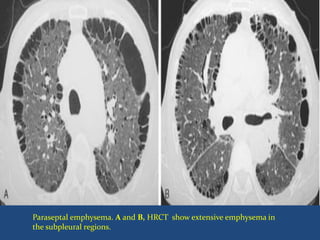

Paraseptal Emphysema

 Also referred to as distal acinar or localized

 Involves the distal portion of the lobule.

 Characteristically adjacent to the visceral pleura and

interlobular septa, within otherwise normal lung

 When these paraseptal cysts exceed 1 cm in size,

with an exceedingly thin wall, they may be termed

bullae.

Paraseptal emphysema. A and B, HRCT show extensive emphysema in

the subpleural regions.